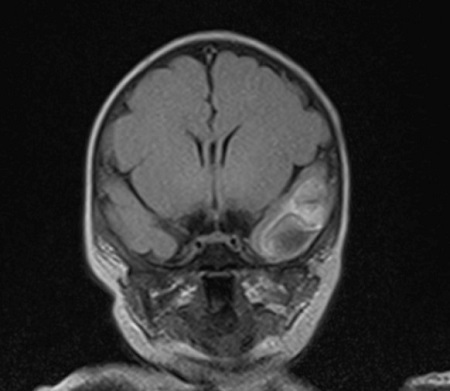

Dentro del estudio de extensión, se realizó electroencefalograma, que resultó normal. También se solicitó RM cerebral, en la que se encontraron áreas de edema y focos hemáticos necrotizantes. Destacaron lesiones en ambos lóbulos temporales y ambas coronas radiadas, siendo estos hallazgos compatibles con encefalitis infecciosa.

Imágenes de RM cerebral en las que se observan áreas de edema parenquimatoso que afectan a ambas coronas radiadas, polo anterior del lóbulo temporal izquierdo y la circunvolución media temporal derecha. En algunas áreas afectadas de los lóbulos temporales se identifican zonas de necrosis cortical. Por otra parte también hay focos de hemorragia subaracnoidea, de predominio en el polo anterior del lóbulo temporal izquierdo, así como mínima hemorragia subdural a nivel de los tentorios y en la vertiente posterior del hoz cerebral.